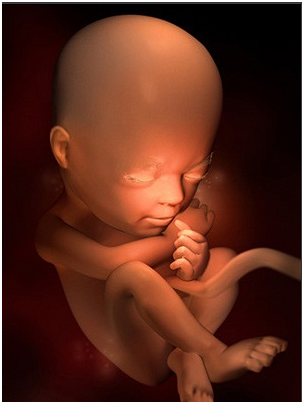

怀孕第34周此时胎儿已经为分娩做好了准备,将身体转为头朝下的姿势。你最近会感觉有一点儿累,这...

怀孕第34周此时胎儿已经为分娩做好了准备,将身体转为头朝下的姿势。你最近会感觉有一点儿累,这... -

怀孕第35周离分娩期越来越近,你可能会有些忐忑不安,甚至是紧张,和丈夫、朋友或自己的妈妈多聊...

怀孕第35周离分娩期越来越近,你可能会有些忐忑不安,甚至是紧张,和丈夫、朋友或自己的妈妈多聊... -

怀孕第36周这时你要多了解一些有关临产征兆的知识,了解什么是宫缩、见红、破水,遇到这些意外该...

怀孕第36周这时你要多了解一些有关临产征兆的知识,了解什么是宫缩、见红、破水,遇到这些意外该... -

怀孕第37周这段时间,你要每周体检一次了。现在宫缩可能出现得更为频繁,如果发现有出血现象,应...

怀孕第37周这段时间,你要每周体检一次了。现在宫缩可能出现得更为频繁,如果发现有出血现象,应... -

怀孕第38周恭喜准妈妈,从现开始你的宝宝已经是足月儿了,随时可能出来和你见面哦!你现在是不是...

怀孕第38周恭喜准妈妈,从现开始你的宝宝已经是足月儿了,随时可能出来和你见面哦!你现在是不是... -